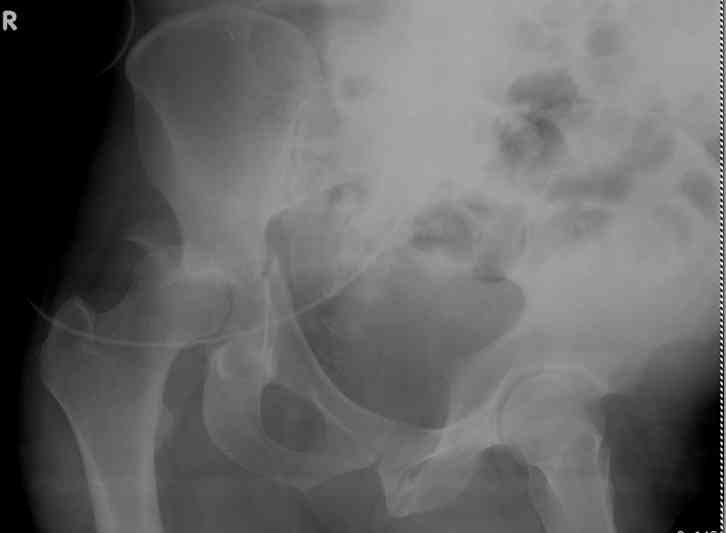

Stabilize anterior column with fluoroscopically guided screw across this end of the transverse fx - As usual, after your reduction of the femoral head, the transverse fx became minimally displaced - slightly gapped without stepoff. I usually (reduce &) stabilize the medial side of the posterior column (transverse fx) with a short plate - before placing the anterior screw unless the transverse fx is undisplaced.

Biggest problem appears to be impaction & comminution of the posterior wall fx site - you've left out some CT cuts. This is not just fragments in joint. It may leave a deficient area, &/or block satisfactory posterior wall reduction.

May need to bone graft elevated articular fragments. Lag screws & more lateral contoured plate to buttress PW. Make sure this reduction is

anatomical.

Timing- get it done whenever the patients is stable and you can preop plan it...we reserve urgent ORIF for irreducible fracture-dislocations and other rare indications...this debris does not seem to impact the head to dome reduction. Doing this at post-injury day 11 and using 40# of traction both seem to invite problems.

I'll include a few images of a similar injury in a similarly large male patient. This patient "showed up" in our ER c/o hip pain 2 months after being treated in the lateral position, without a quality reduction, without an anterior column transverse supporting implant, with an unbalanced plate applied too medially, with insufficient caudal segment fixation...it took over 8 hours and a 3+ l blood loss to debride the callus from front then

back, excise the HO, release his sciatic nerve, reduce the head-transverse-wall, and fix it...and now it's a staging procedure.

The 2nd example is of a motorcyclist with a transverse fracture-dislocation...he had a closed attempted reduction and placed in traction but the manipulative reduction was not concentric (not unusual for this injury pattern)...so the traction was adjusted to be just enough to disengage the head from the fracture (12#) until he could be cleared for surgery one day after injury...he was treated "urgently" then with a prone KL, clean the fracture, reduce and clamp it, screw it, support with a balanced plate, close, and enjoy...2-3hours, 400cc EBL, blah, blah, blah..